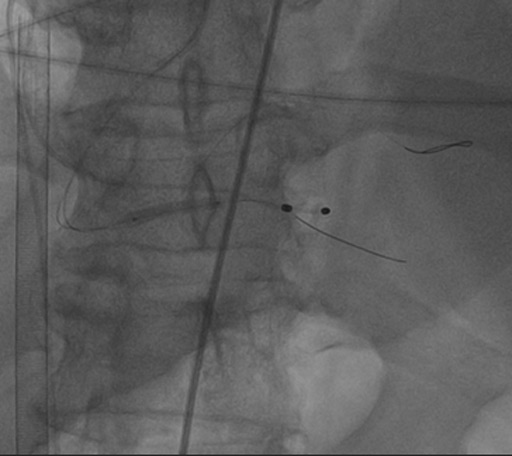

Wiring the LAD

First stent was implanted

We see a contrast stagnation after the LAD stenting

The next stage was of RCA distal part stenting.